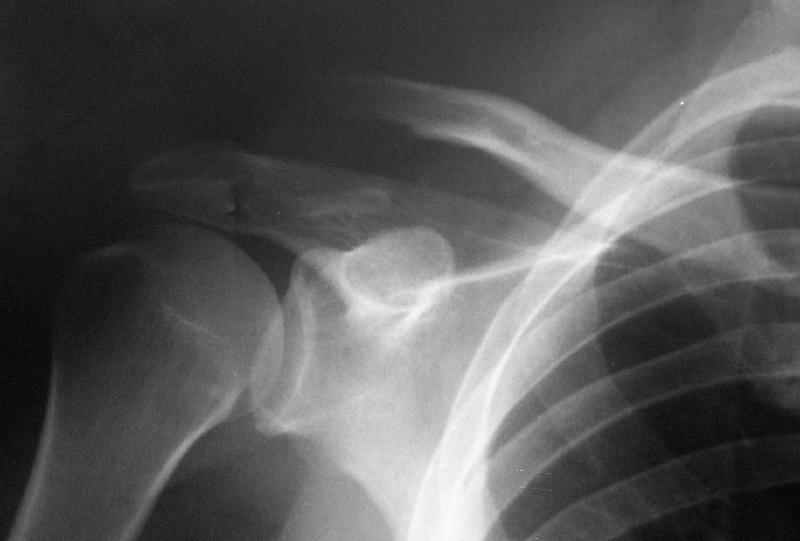

Судя по смещению центрального отломка ключицы, у больного разорваны и ключично- клювовидные связки - 2B тип( классификация см. orthopedic knowledge online rev. R. Dopirak may 2004 http://www.aaos.org/oko)

При выборе тактики (консервативной или оперативной) кроме Рг, полезно было бы знать какбольной сам оценивает своё состояние в данный момент на предмет болей, функции плечевого сустава после проведенного лечения в аппарате (ведь мы спасаем не Рг, а функцию) Ежели такая жизнь его не устраивает, то хирургия становится логичным продолжением процесса.

Думаю, что закрытая перкутанная фиксация спицами только вряд ли будет эффективной в данном случае и чтобы *не наступать на одни грабли дважды*

нужно открыть место перелома и убрать все рубцы. Выбор метода фиксации: я бы не стал применять пластину - слишком обширное скелетирование отломков с понятными нежелательными последствиями, в отношении hook plate - не вижу целесообразности в её применении и вот почему: с одной стороны она